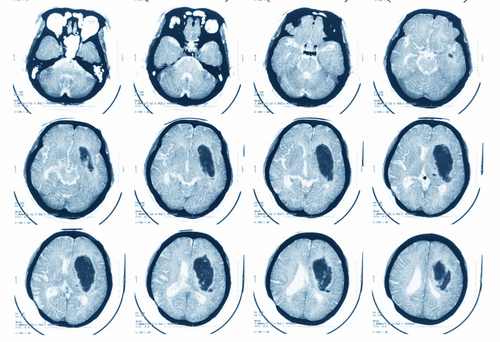

Life of a 41-year-old woman has been saved after successful removal of a cyst weighing 200gm from her brain at a city hospital here, doctors said on Thursday.

According to the hospital authorities, Shanti got diagnosed of the problem couple of months back. Along with tremendous pain, the patient was unable to stand or walk without support.Doctors advised MRI of her head which unveiled a large hollow stone-like tumour/ cyst inside her brain. It had taken the shape of an egg with a hard surface, with brain cells all around it.After admission at the Asian Institute of Medical Sciences (AIMS), a team of doctors was constituted and accordingly the decision was taken to perform the surgery."We tested the foreign matter and discovered that it was caused by some parasite. Such parasites in the brain are known to cause soft balloon like cysts in some patients, but this type of hard structure and size has never been reported in medical literature," said Mukesh Pandey, Senior Consultant Neurosurgeon at AIMS.

During the surgery, the doctors had to be extra careful in removing the cyst as it contained toxic fluids as well. They said that if the fluid had leaked out into the brain, it could have caused severe reactions or formed more cysts, which could have killed the patient.The surgery took about four hours."It was a challenging surgery as we had to remove this egg-shaped cyst completely and in one piece without causing any damage to the brain. It was about 200gm in weight and measured 8cmX8cm in size," said Kamal Verma, Director of Neurosurgery at AIMS.According to the doctor, the patient took couple of weeks to recover and now is fit to do her daily chores."Shanti can carry out her daily chores smoothly and has no problems with her speech now. She thanked AIMS for giving her a new life," said one of the doctors.